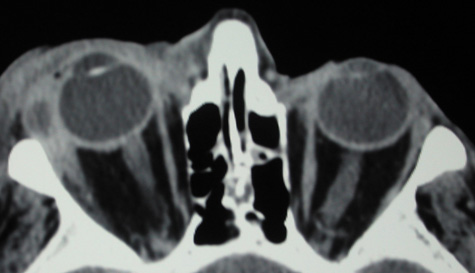

CT is particularly useful for imaging orbital and subperiosteal abscesses. Because the periorbit is not adherent to the orbital walls except at the suture lines, an abscess lifts the periorbit, creating a convexity in the orbital periosteum (Fig. 16). Usually subperiosteal abscess formation occurs adjacent to the involved sinus,25,64 but occasionally it occurs at a remote location such as the superolateral orbit.65 Gas may be found within a subperiosteal abscess or within the orbit, arising either from gas-forming bacilli or free communication with sinus air or from prior trauma (Fig. 17). 57,66 CT cannot accurately predict whether a subperiosteal mass represents exudate, inflammatory transudate, or hematoma.67,68

Fig. 16. Computed tomography showing subperiosteal abscess formation. Note elevation of orbital periosteum and convexity as pus elevates periorbit from the medial orbital wall.